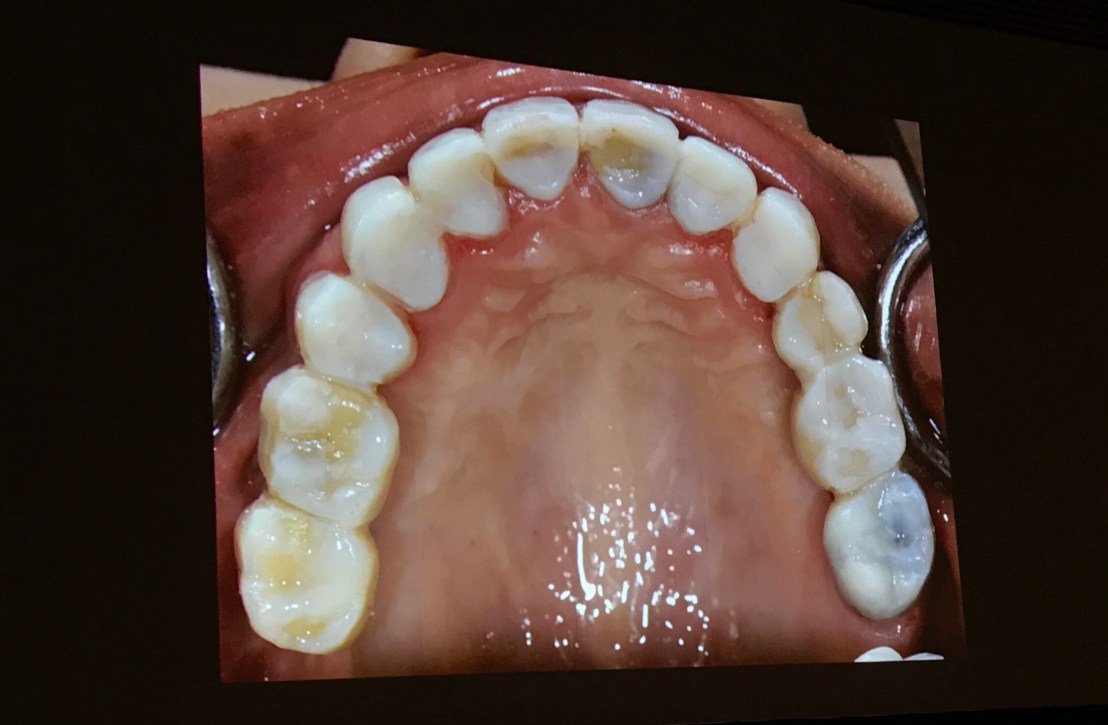

Intra-Oral